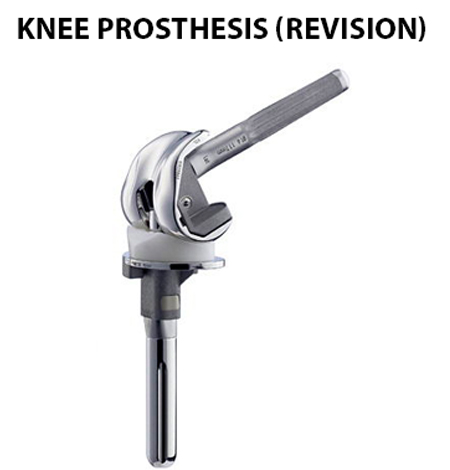

Revision Total Knee Replacement

Primary Total Knee replacement is a surgery where the damaged knee joint is replaced with an implant or a prosthesis made of metal or plastic components.

Most of the primary total knee replacement surgeries are successful, over time certain problems like implant wear, infection, instability, stiffness, fractures and loosening may require a revision procedure to replace the original components.